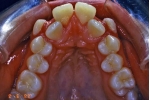

初診時